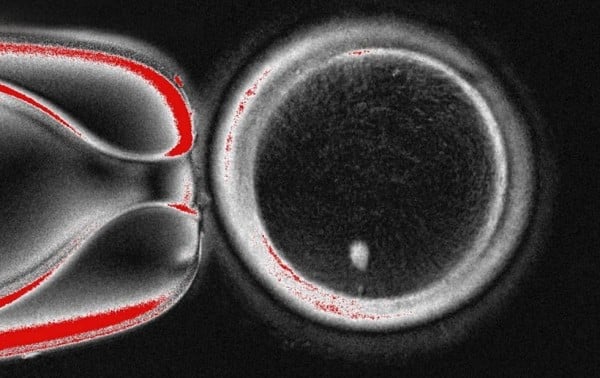

Científicos de Oregón utilizaron células de piel humana para crear óvulos fertilizables, un paso en la búsqueda de desarrollar óvulos o espermatozoides cultivados en laboratorio para ayudar a las personas a concebir en el futuro.

Sin embargo, el experimento resultó en anomalías en los cromosomas, lo que llevó al equipo de la Universidad de Salud y Ciencia de Oregon (o Oregon Health & Science University, OHSU) a advertir que podría tomar una década de investigación adicional antes de que tal técnica esté lista para ensayos en personas.

El trabajo publicado el martes en Nature Communications puede ofrecer lecciones mientras los científicos intentan aprender a crear óvulos y espermatozoides en un laboratorio para personas infértiles o para ayudar a parejas del mismo sexo a tener hijos genét